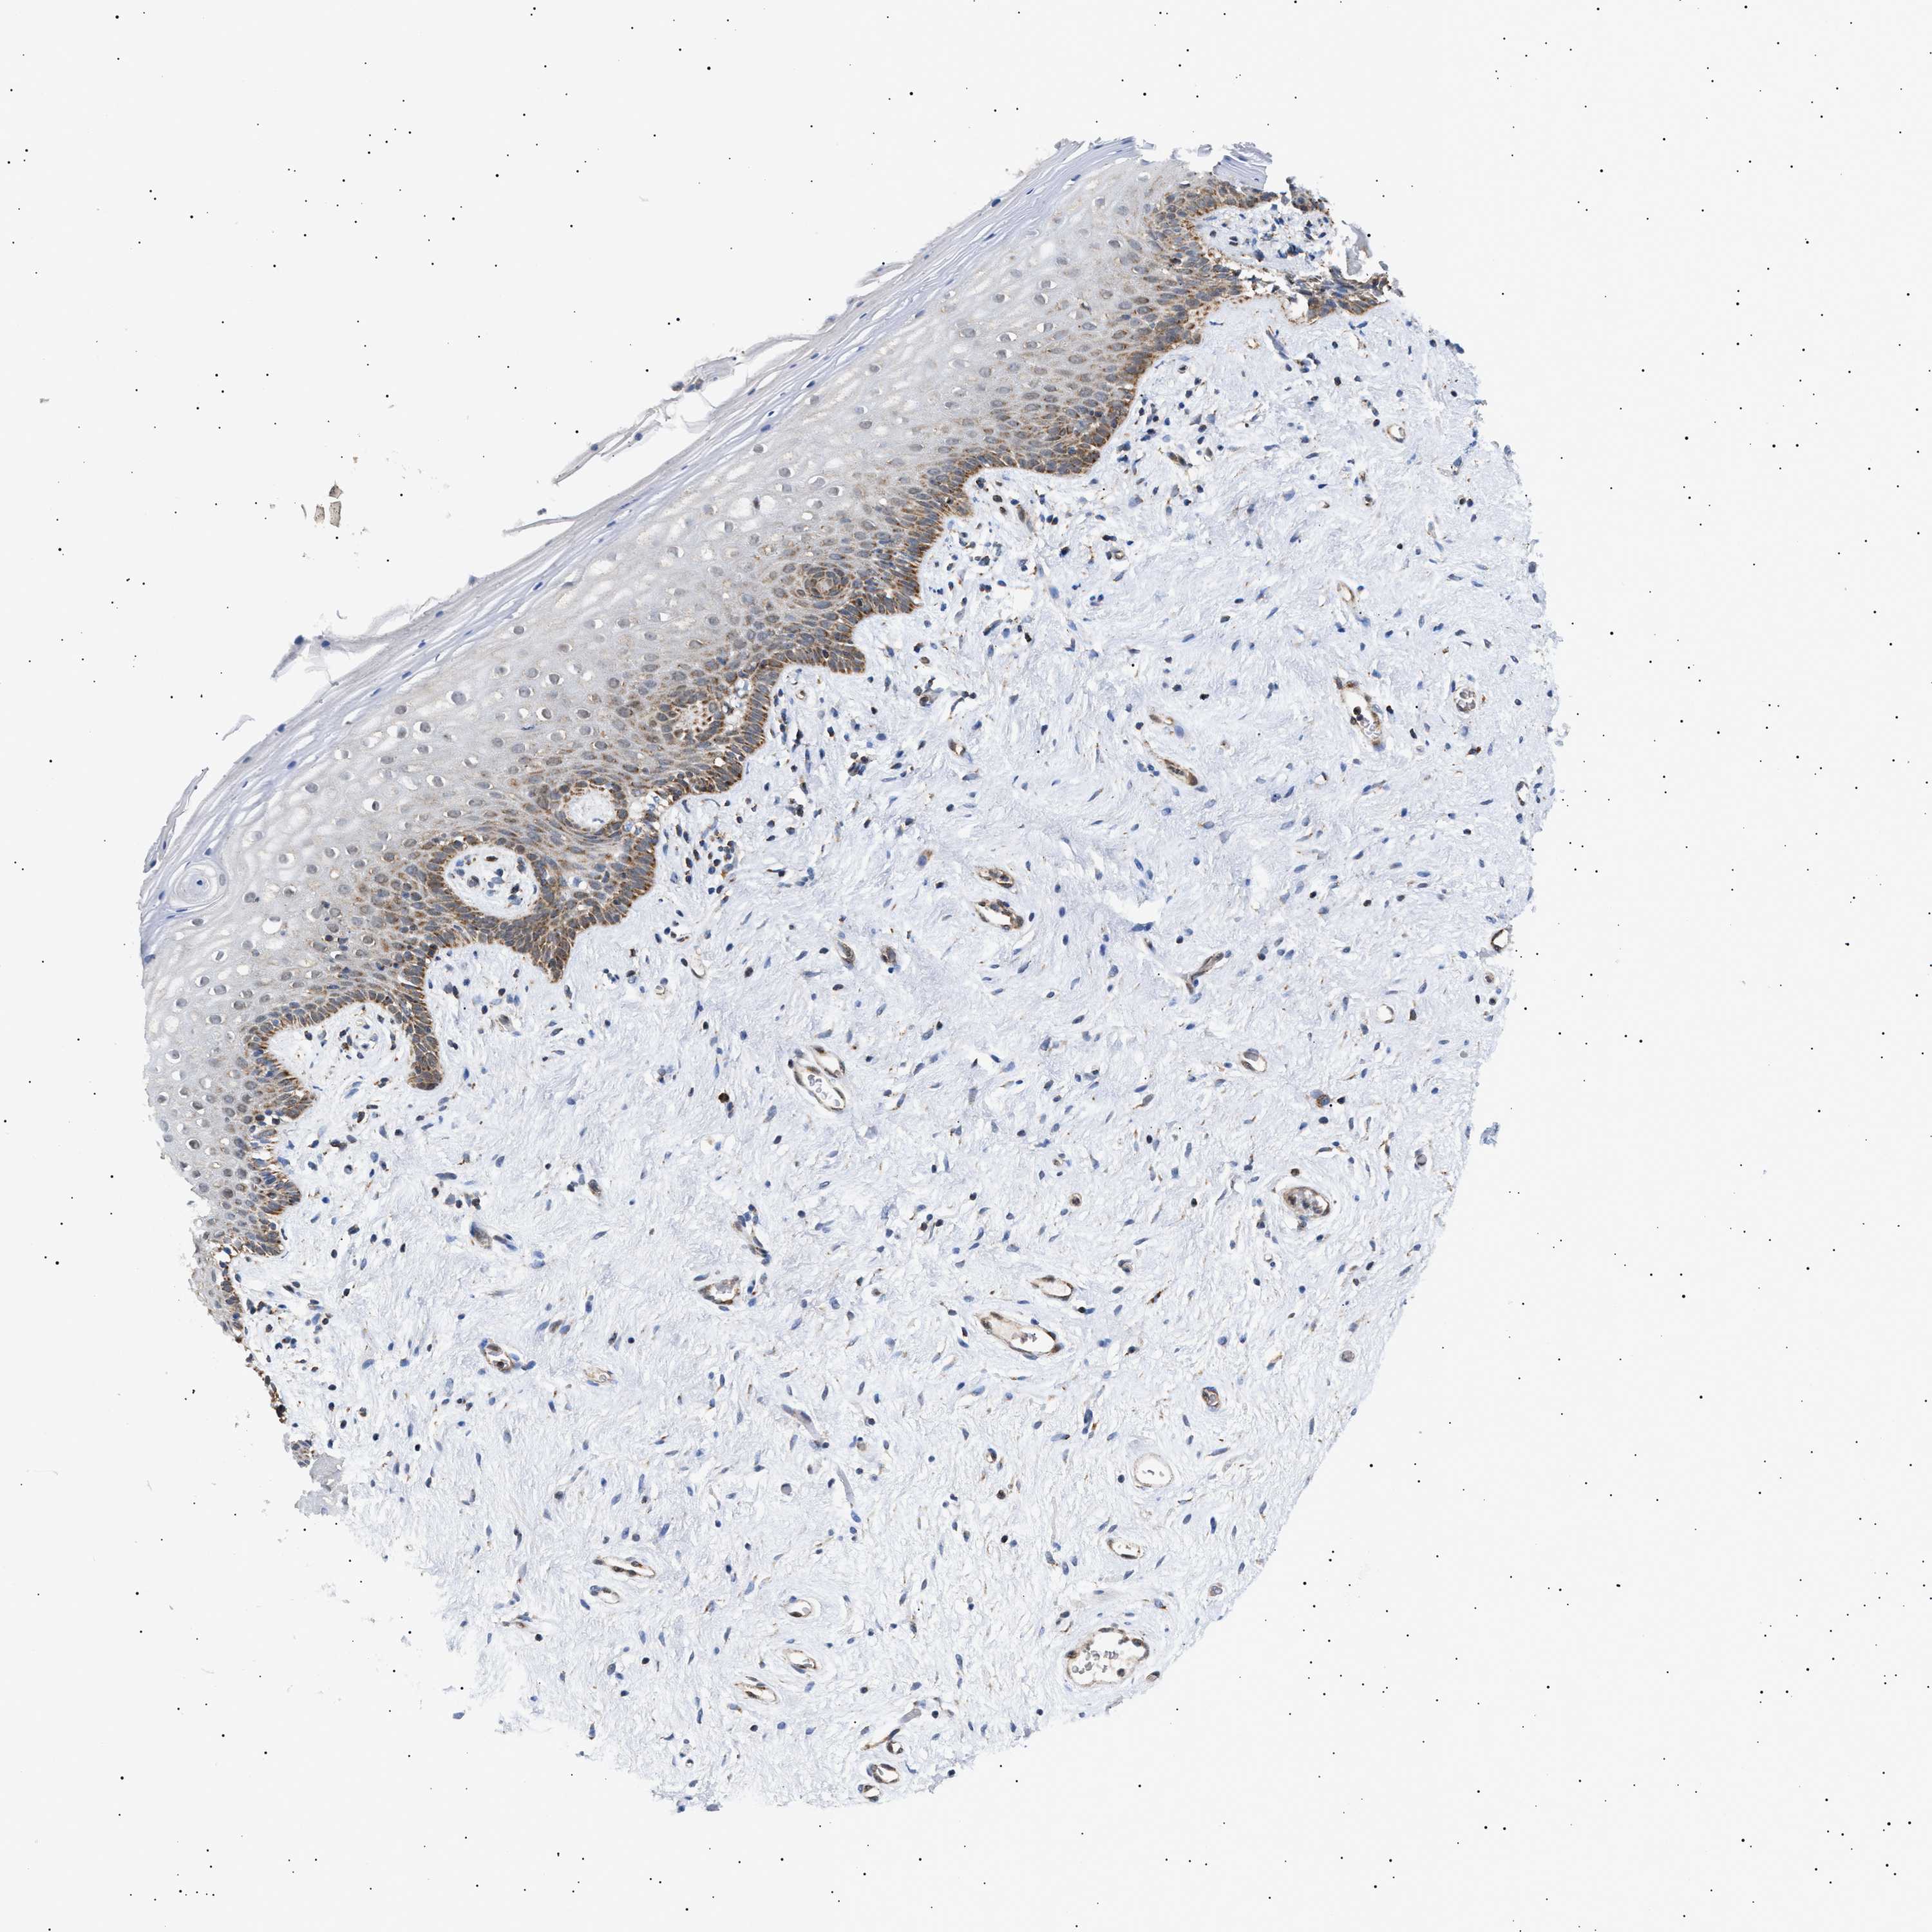

VAGINA - Antibody stainingi

Antibody staining in the annotated cell types in the current human tissue is reported as not detected, low, medium, or high, based on conventional immunohistochemistry profiling in selected tissues. This score is based on the combination of the staining intensity and fraction of stained cells.

Each image is clickable and will lead to virtual microscopy that enables deeper exploration of all samples and also displays staining intensity scores, fraction scores and subcellular localization as well as patient and tissue information for each sample.

Antibody HPA021798Antibody HPA022002Antibody HPA022992

Squamous epithelial cells LowLowMedium